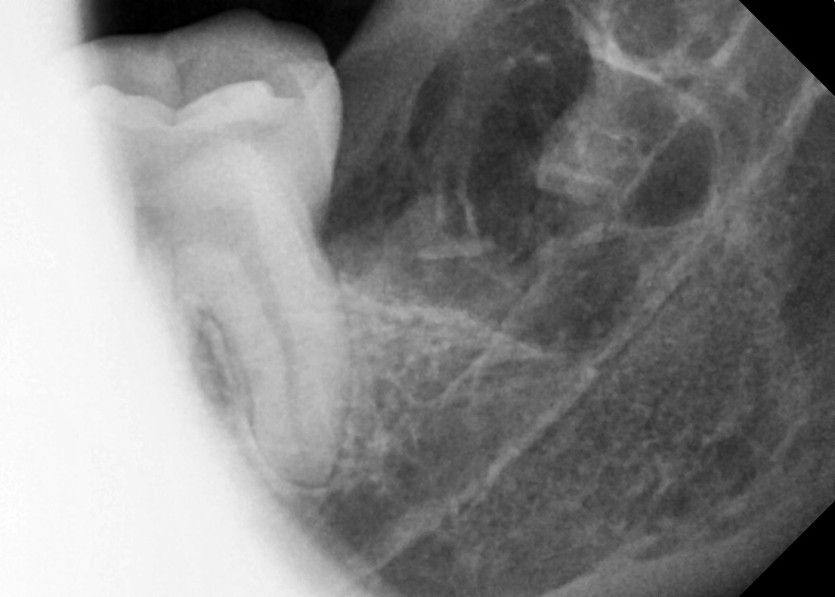

#18,28,38,48 사랑니 발치

구강 외과 전문의가 당일 발치했습니다.